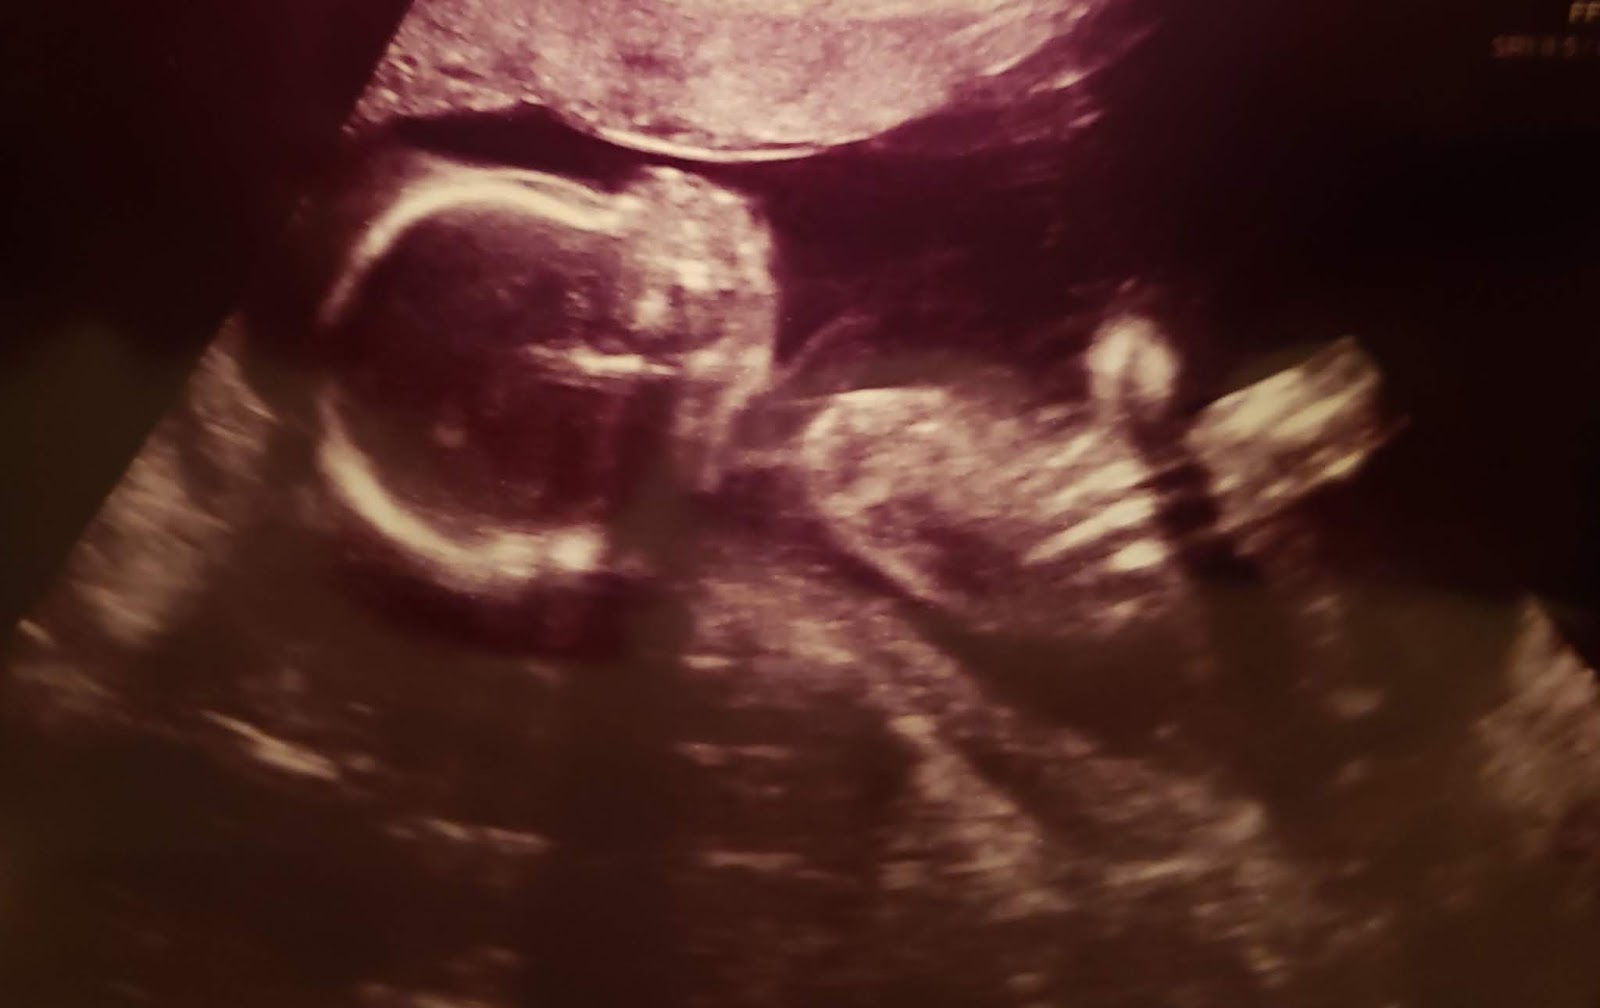

Baby Chris is 19 Weeks Old

19 weeks after fertilization (21 weeks LMP), Baby Chris is 10.5 inches long and weighs just under 13 ounces; roughly the size of a large carrot. His or her movements are clearly felt by the mother, as “initial fluttering movements turn into full-fledged kicks and nudges.”